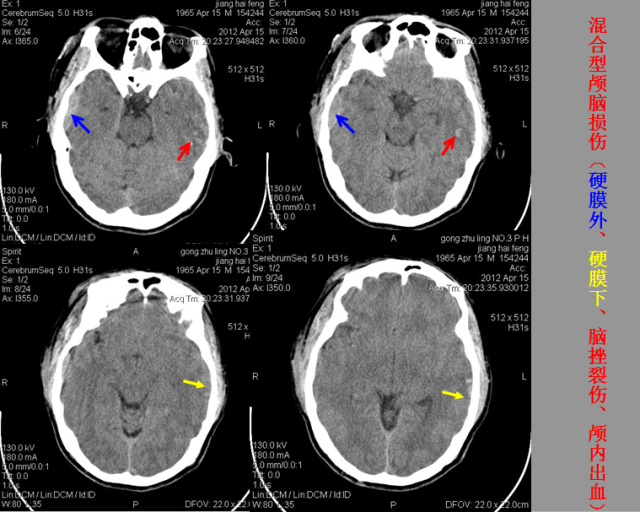

急性颅脑损伤篇

急胸症篇